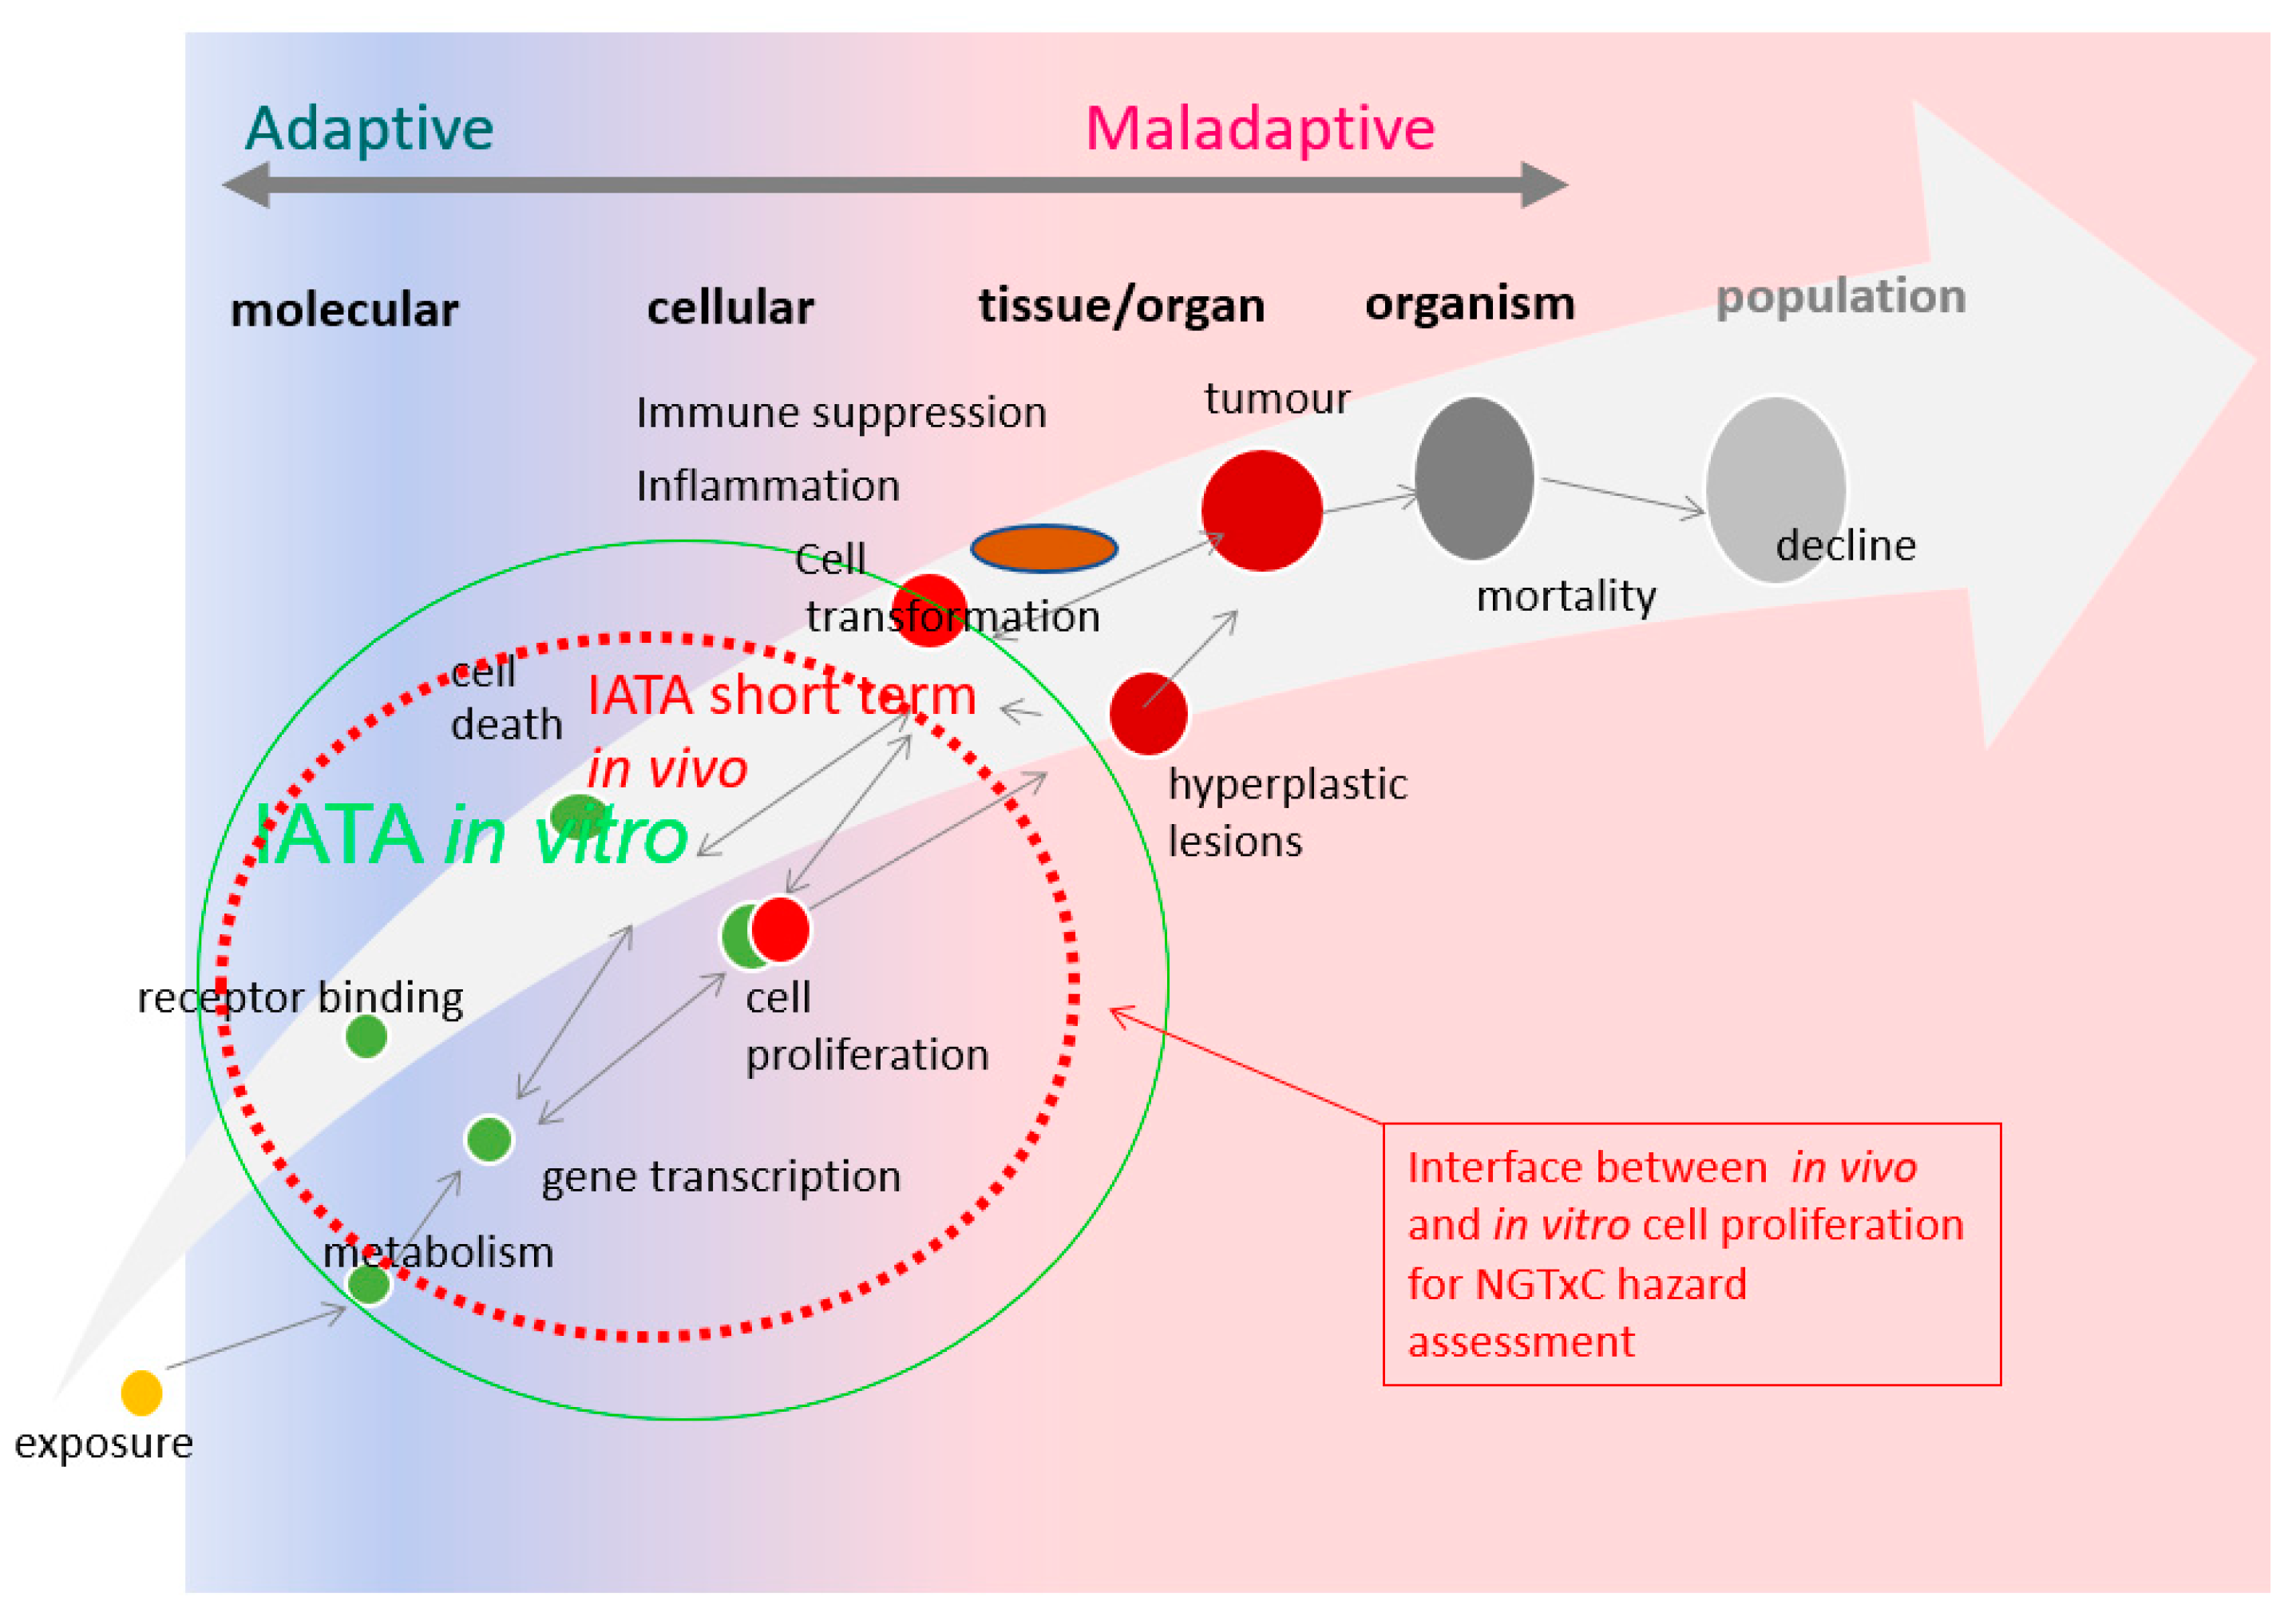

4. Application of Cell Proliferation Assay Tools in the NGTxC IATA: Proposed Way Forward